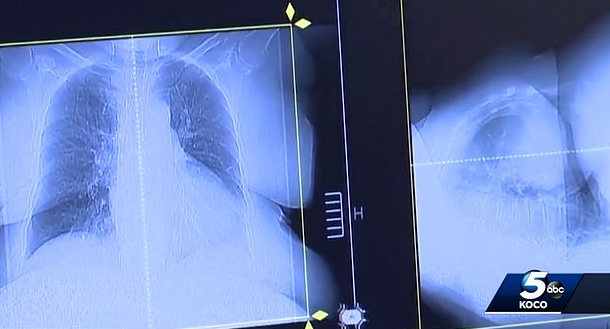

이 영상에 따르면 조 티펜스씨는 2016년 말기 소세포폐암 진단을 받았으며 다음 해 1월 암세포가 간과 췌장, 위 등에 퍼져 3개월 시한부라는 이야기를 들었습니다. 이에 한 수의사가 그에게 개 구충제를 복용하고 6주 만에 뇌암이 나은 환자 이야기를 전하며 펜벤다졸 복용을 권했는데요 이후 펜벤다졸을 복용한 티펜스는 3개월 뒤 암세포가 깨끗이 사라졌다고 합니다. 과연 이러한 암의 완치가 대부분의 사람들에게 일어날 수 있을까요?